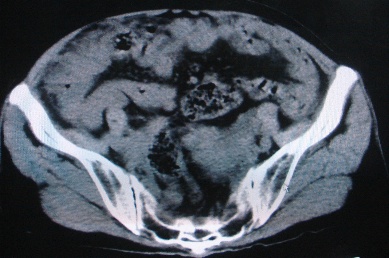

以下是引用卜一在2007-4-30 15:29:00的发言:[br]子宫明显增大,不规则,子宫壁不规则增厚,子宫腔明显缩小,子宫右侧软组织团块与子宫关系密切,内见低密度坏死区。考虑:子宫癌并周围侵润。